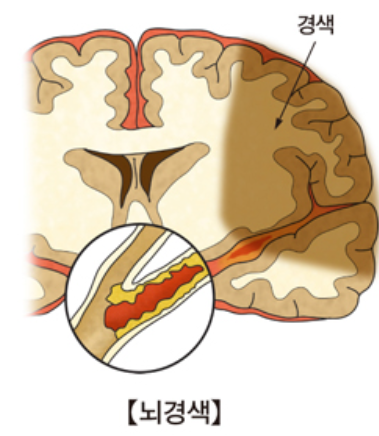

뇌경색은 뇌세포가 죽어가는 과정으로 즉시 치료하지 않을 경우 생명을 앗아갈 수 있는 치명적인 질환 중 하나입니다. 뇌졸중 종류 중 하나인 뇌경색은 뇌혈관이 막혀 뇌에 혈액순환이 제대로 이루어지지 않아 발생하는 증상인데요.

뇌졸중이 심각해지면 뇌 벽 내부의 약한 부분이 터져 뇌 안에 출혈이 생기기 때문에 미리 예방하고 빠르게 처치하는 것이 매우 중요합니다. 때문에 뇌경색 초기 증상이 의심된다면 빠르게 가까운 병원으로 가보는 것을 권장드립니다.